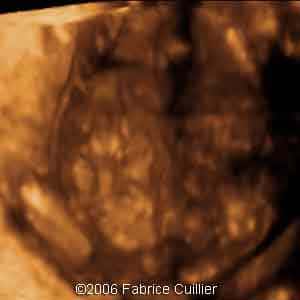

3D coronal view at 17 weeks

3